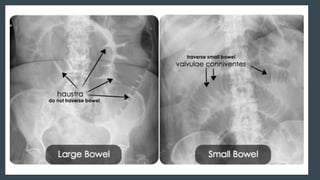

RADIOLOGICAL PICTURE

Small Bowel Obstruction

Central distention (GAS)

Valvulae conniventes

Ladder-like dilatation

Small diameter

Large Bowel Obstruction

Peripheral distention “Picture frame”

More gross distention

Haustral indentation & large diameter

RADIOLOGICAL PICTURE Small BowelObstruction Central distention (GAS) Valvulae conniventes Ladder-like dilatation Small diameter Large Bowel Obstruction Peripheral distention “Picture frame” More gross distention Haustral indentation & large diameter